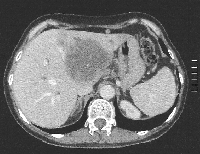

Πρόκειται για γυναίκα ασθενή 56 ετών η οποία, στα πλαίσια διερεύνησης αποφρακτικού ικτέρου, διαπιστώθηκε ότι έπασχε από μονήρες ενδοηπατικό χολαγγειοκαρκίνωμα μεγέθους 7,5 cm που οποίο καταλάμβανε τα τμήματα 1, 2, 3, 4a, 4b, 5 (μερικώς) και 8 (μερικώς), διηθούσε την αριστερή και τη μέση ηπατική φλέβα, είχε προκαλέσει θρόμβωση του αριστερού κλάδου της πυλαίας φλέβας και εφίππευε στο δεξιό κλάδο της πυλαίας φλέβας (εικόνα 1). Η άρση της χολόστασης προεγχειρητικά επιτεύχθηκε με ERCP και τοποθέτηση stent δεξιού χοληδόχου πόρου. Πραγματοποιήθηκε προεγχειρητική ηπατική ογκομέτρηση με ανάλυση MeVis (εικόνα 2). Διεγχειρητικά εξασφαλίστηκε η δυνατότητα ολικού αγγειακού αποκλεισμού (εικόνα 3). Διενεργήθηκε αριστερή εκτεταμμένη ηπατεκτομή. Ο όγκος αφαιρέθηκε πλήρως, με άθικτη κάψα (εικόνα 4). Το ηπατικό υπόλειμμα ανήλθε στο 31% του αρχικού όγκου του οργάνου (εικόνα 5). Η ογκομετρική CT την 4η μετεγχειρητική εβδομάδα ήταν ικανοποιητική (εικόνα 6). Η ασθενής πήρε εξιτήριο την 7η μετεγχειρητική ημέρα. Έλαβε μετεγχειρητική χημειοθεραπεία (GEMOX).